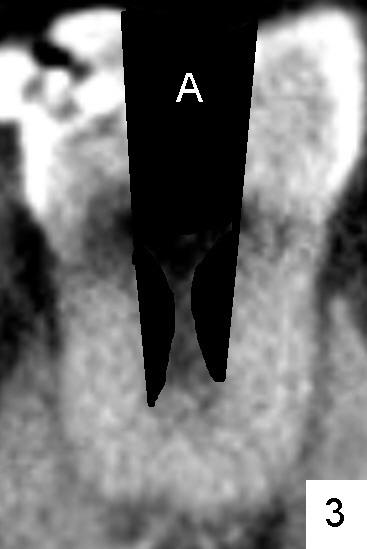

近中根上三分之一好像是单根(图二*以及图一左上),快到中三分之一根管一分为二(图二箭头:B颊侧,L舌侧;图四左上箭头),中三分之一近中舌侧根管仿佛有两个侧枝根管(图五箭头),尽管下三分之一根管又融合(图八*,图七左上横断面:单个扁根管),中三分之一近中两个根管必须分别清洗(图六红色粉红色:两个扩大针),之前应该扩大根管进口(图三A: access,与图二对比)。如果偷懒或者事先无知而遗留一个根管,往后处理并发症可麻烦。本例病人马上要到老美牙学院上学了。

有两个疑问:第一,根尖三角区(delta; 图八)根管(*)似乎又分裂了(箭头),冲洗是不是要达到那里,扩大针是不是要交叉一下(图九)。